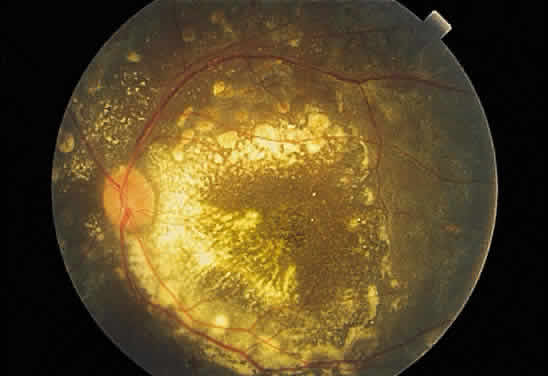

Necrotic retina has a white appearance. Necrosis may result from a variety of inflammatory conditions, including viral, fungal, and protozoal (Toxoplasma) retinitis. Each type of retinitis appears, in part, as a white retinal lesion. Cytomegalovirus retinitis (Fig. 24) resembles a pizza pie with an admixture of white (retinal inflammation) and red (hemorrhage) colors (Fig. 25). The retinal abscesses of fungal retinitis are white. Likewise, the satellite lesion of retinochoroiditis caused by active Toxoplasma (the choroidal inflammation is merely in response to the primary retinal infection) is white (Fig. 26). The white appearance of a lesion from inactive Toxoplasma results from the destruction of neurosensory retina, retinal pigment epithelium, and choroid to permit a direct view of the sclera (Fig. 27). Necrosis in retinal-derived neoplasms is white; the appearance of regressed (necrotic) retinoblastoma often is described as “cottage cheese.”10

Fig. 24. A. Histologic section of cytomegalic inclusion retinitis. The characteristic inclusions cannot be seen at this magnification. Compare the appearance of viable healthy retina (left of arrow) with necrotic retina (right of arrow). The admixture of necrotic retina (clinically white) with hemorrhage (clinically red) accounts for the ophthalmoscopic appearance of this entity. B. Cytomegalovirus retinitis. Histologic section of sensory retina demonstrating massive necrosis involving all layers. (Courtesy of Ralph C. Eagle Jr, MD, Philadelphia, PA)

Fig. 25. Fundus photograph of cytomegalovirus retinitis with the classic admixture of retinal infection (white) and hemorrhage, giving the so-called “pizza-pie” appearance.